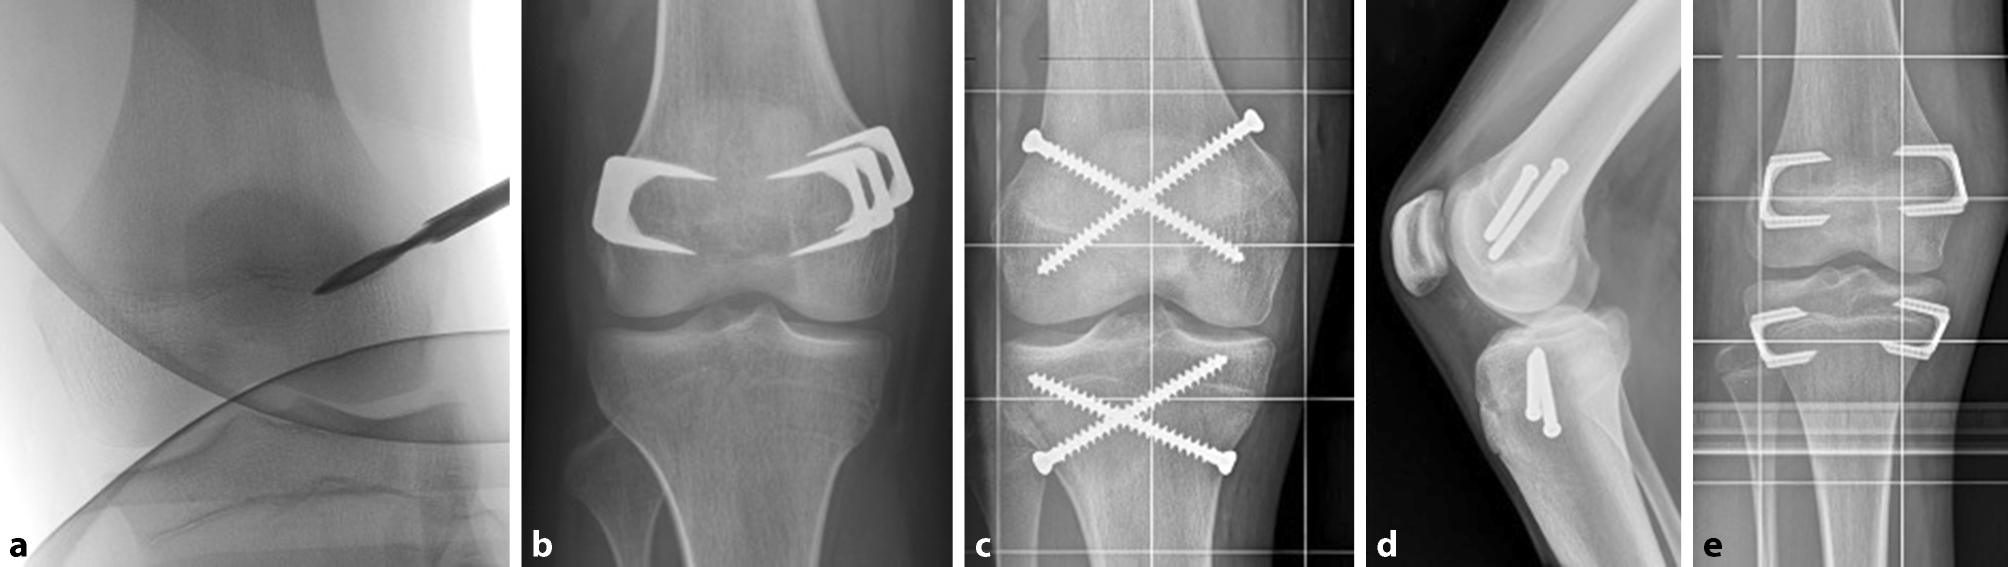

The principle of epiphysiodesis (ED) is to achieve a temporary or permanent growth arrest at the physis. In 1933, Dr. Dallas Phemister introduced the first surgical method to arrest the growth of the physis. According to this uninstrumented technique, a rectangular piece of bone including a part of the growth plate is osteotomized, rotated 180° and reinserted. This technique forms an osseous connection in the region of the growth plate and is therefore a definitive procedure. Performed on both sides of the growth plate (medial and lateral), this leads to a permanent growth arrest by creation of a bony bridge [32]. Due to the invasiveness of this surgical technique, modifications in terms of a percutaneous epiphysiodesis gained popularity in the 1980s. Bowen and Johnson described a technique in which the peripheral third of the physis is removed with a curette using minor incisions [33]. The originally described procedure by Canale uses a drill and pneumatic burrs to ream the growth plate. Through minimal incisions, a drill is passed several times through the physis in order to destroy the physis (Fig. 3a). Afterwards a curette is used to remove the growth plate. Approximately 50% of the growth plate should be removed to ensure growth arrest [34].

Fig. 3

Currently used epiphysiodesis techniques. a Percutaneous Canale epiphysiodesis, b Blount staples, c, d percutaneous epiphysiodesis using transphyseal screws (PETS), e new implant RigidTackTM

Haas discovered in a series of animal experiments that a reversible slowing down of physeal growth is possible by implanting a wire loop in the area of the distal femoral physis. He also noticed that growth resumes as soon as the wire loop breaks. Further development using this principle resulted in the use of staples for temporary growth arrest. Blount popularized this technique and published first clinical results. Three extraperiosteal staples are placed across the lateral and medial physis to create a temporary arrest (Fig. 3b). Growth would resume after removal of the staples [35]. Nevertheless, the promising idea of a temporary growth arrest was abandoned after several reports of permanent growth arrest, angular deformity, or rebound growth after staple removal. Therefore this technique is considered a permanent epiphysiodesis [13] (Table 3). Other methods include the placement of transphyseal screws (percutaneous epiphysiodesis using transphyseal screws—PETS (Fig. 3c, d), described by Metaizeau et al. [36]. This method using fully threaded stainless steel screws may be more effective in the distal femur compared with the proximal tibia [37].